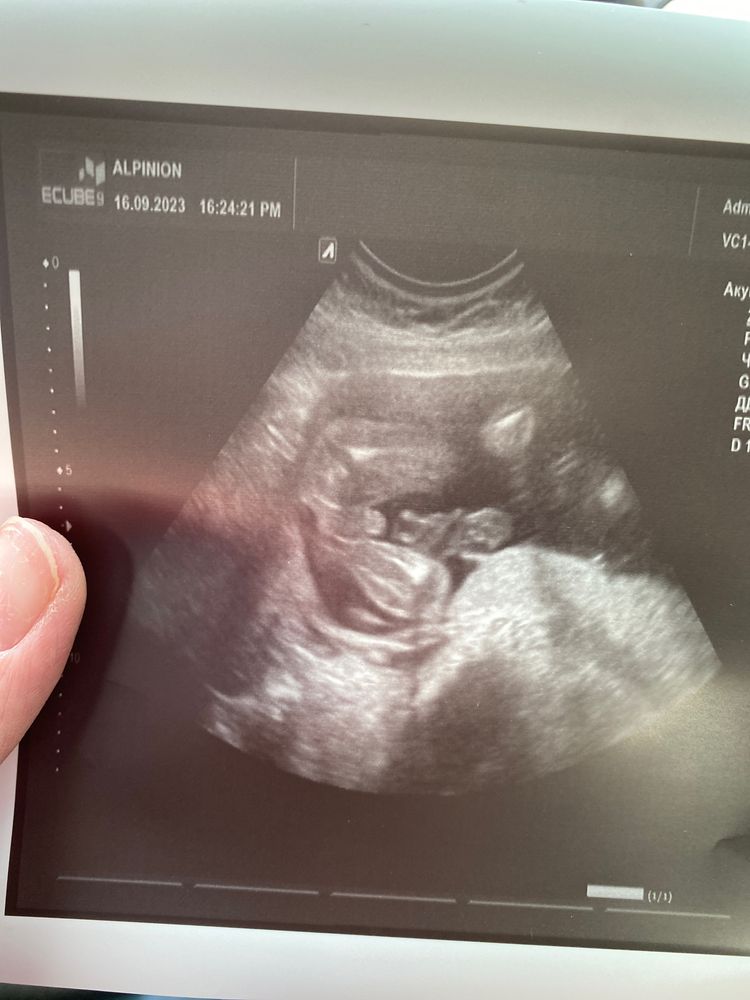

19 неделя. Прошла второй скриннинг) Узнала пол, убедилась, что все слава Богу хорошо) Немного в шоке, что буду мамой сыночка. Так волнительно. До последнего была уверненна, что там еще одна дочка. Смотрю мальчишки особо не сркываются у мамочек в животиках. Первый кадр моего УЗИ - жопка малыша с выставленными напоказ прелестями) Было очень смешно, когда узистка повернула ко мне монитор, потом резко развернула и спросила - вам пол говорить или вы уже сами все увидели?))) Теперь задача - выбрать имя. Дала задание мужу и дочке написать список имен, которые им нравятся, сама уже тоже написала. Будет сидеть подбирать. Думаю пора собираться с мыслями и перебирать дочкины малышковые вещи и вещи племянников. Чтобы понять, что нужно докупать.Заодно от тревожных мыслей занятие отвлечет. О, и я уже купила комбинезон с шапочкой на выписку, теперь нужно к нему подобрать тепленький конверт или кокон.